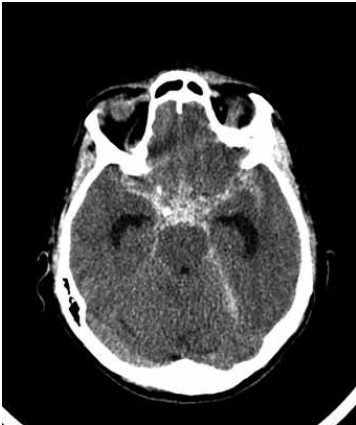

Paciente do sexo feminino, de 48 anos de idade, é trazida ao pronto-socorro com cefaleia e rebaixamento do nível de consciência. Foi submetida à tomografia computadorizada de crânio que evidenciou o achado a seguir:

(Arquivo pessoal; imagem usada com autorização)